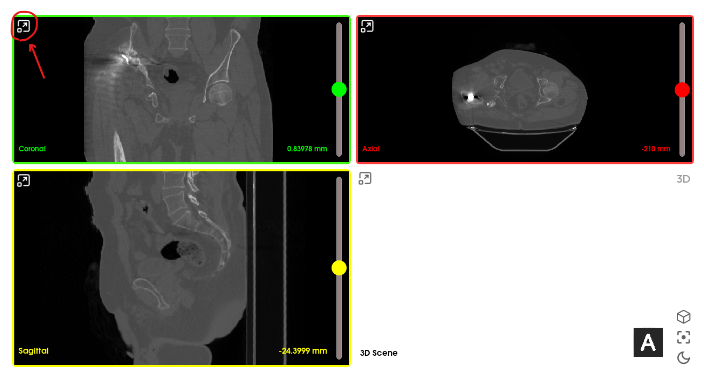

Main dashboard

- The main application dashboard is divided into five main parts:

- Views: 3D and 2D views for interaction and visualization.

Views

There are four main types of views: Coronal, Axial, Sagittal, and 3D Scene.

Minimize/Maximize view: To maximize/minimize any specific view, click the button at the top left corner located within the view.

Reset field of view: Use sliders to navigate between different slices. To reset to the default slice of any 2D view, double right-click inside that view, a menu will appear, then click "Reset field of view".